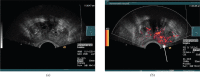

Transrectal ultrasound (TRUS) was first developed in the 1970s. TRUS-guided biopsy, under local anaesthetic and prophylactic antibiotics, is now the most widely accepted method to diagnose prostate cancer. However, the sensitivity and specificity of greyscale TRUS in the detection of prostate cancer is low. Prostate cancer most commonly appears as a hypoechoic focal lesion in the peripheral zone on TRUS but the appearances are variable with considerable overlap with benign lesions. Because of the low accuracy of greyscale TRUS, TRUS-guided biopsies have become established in the acquisition of systematic biopsies from standard locations. The number of systematic biopsies has increased over the years, with 10-12 cores currently accepted as the minimum standard. This article describes the technique of TRUS and biopsy and its complications. Novel modalities including contrast-enhanced modes and elastography as well as fusion techniques for increasing the sensitivity of TRUS-guided prostate-targeted biopsies are discussed along with their role in the diagnosis and management of prostate cancer.